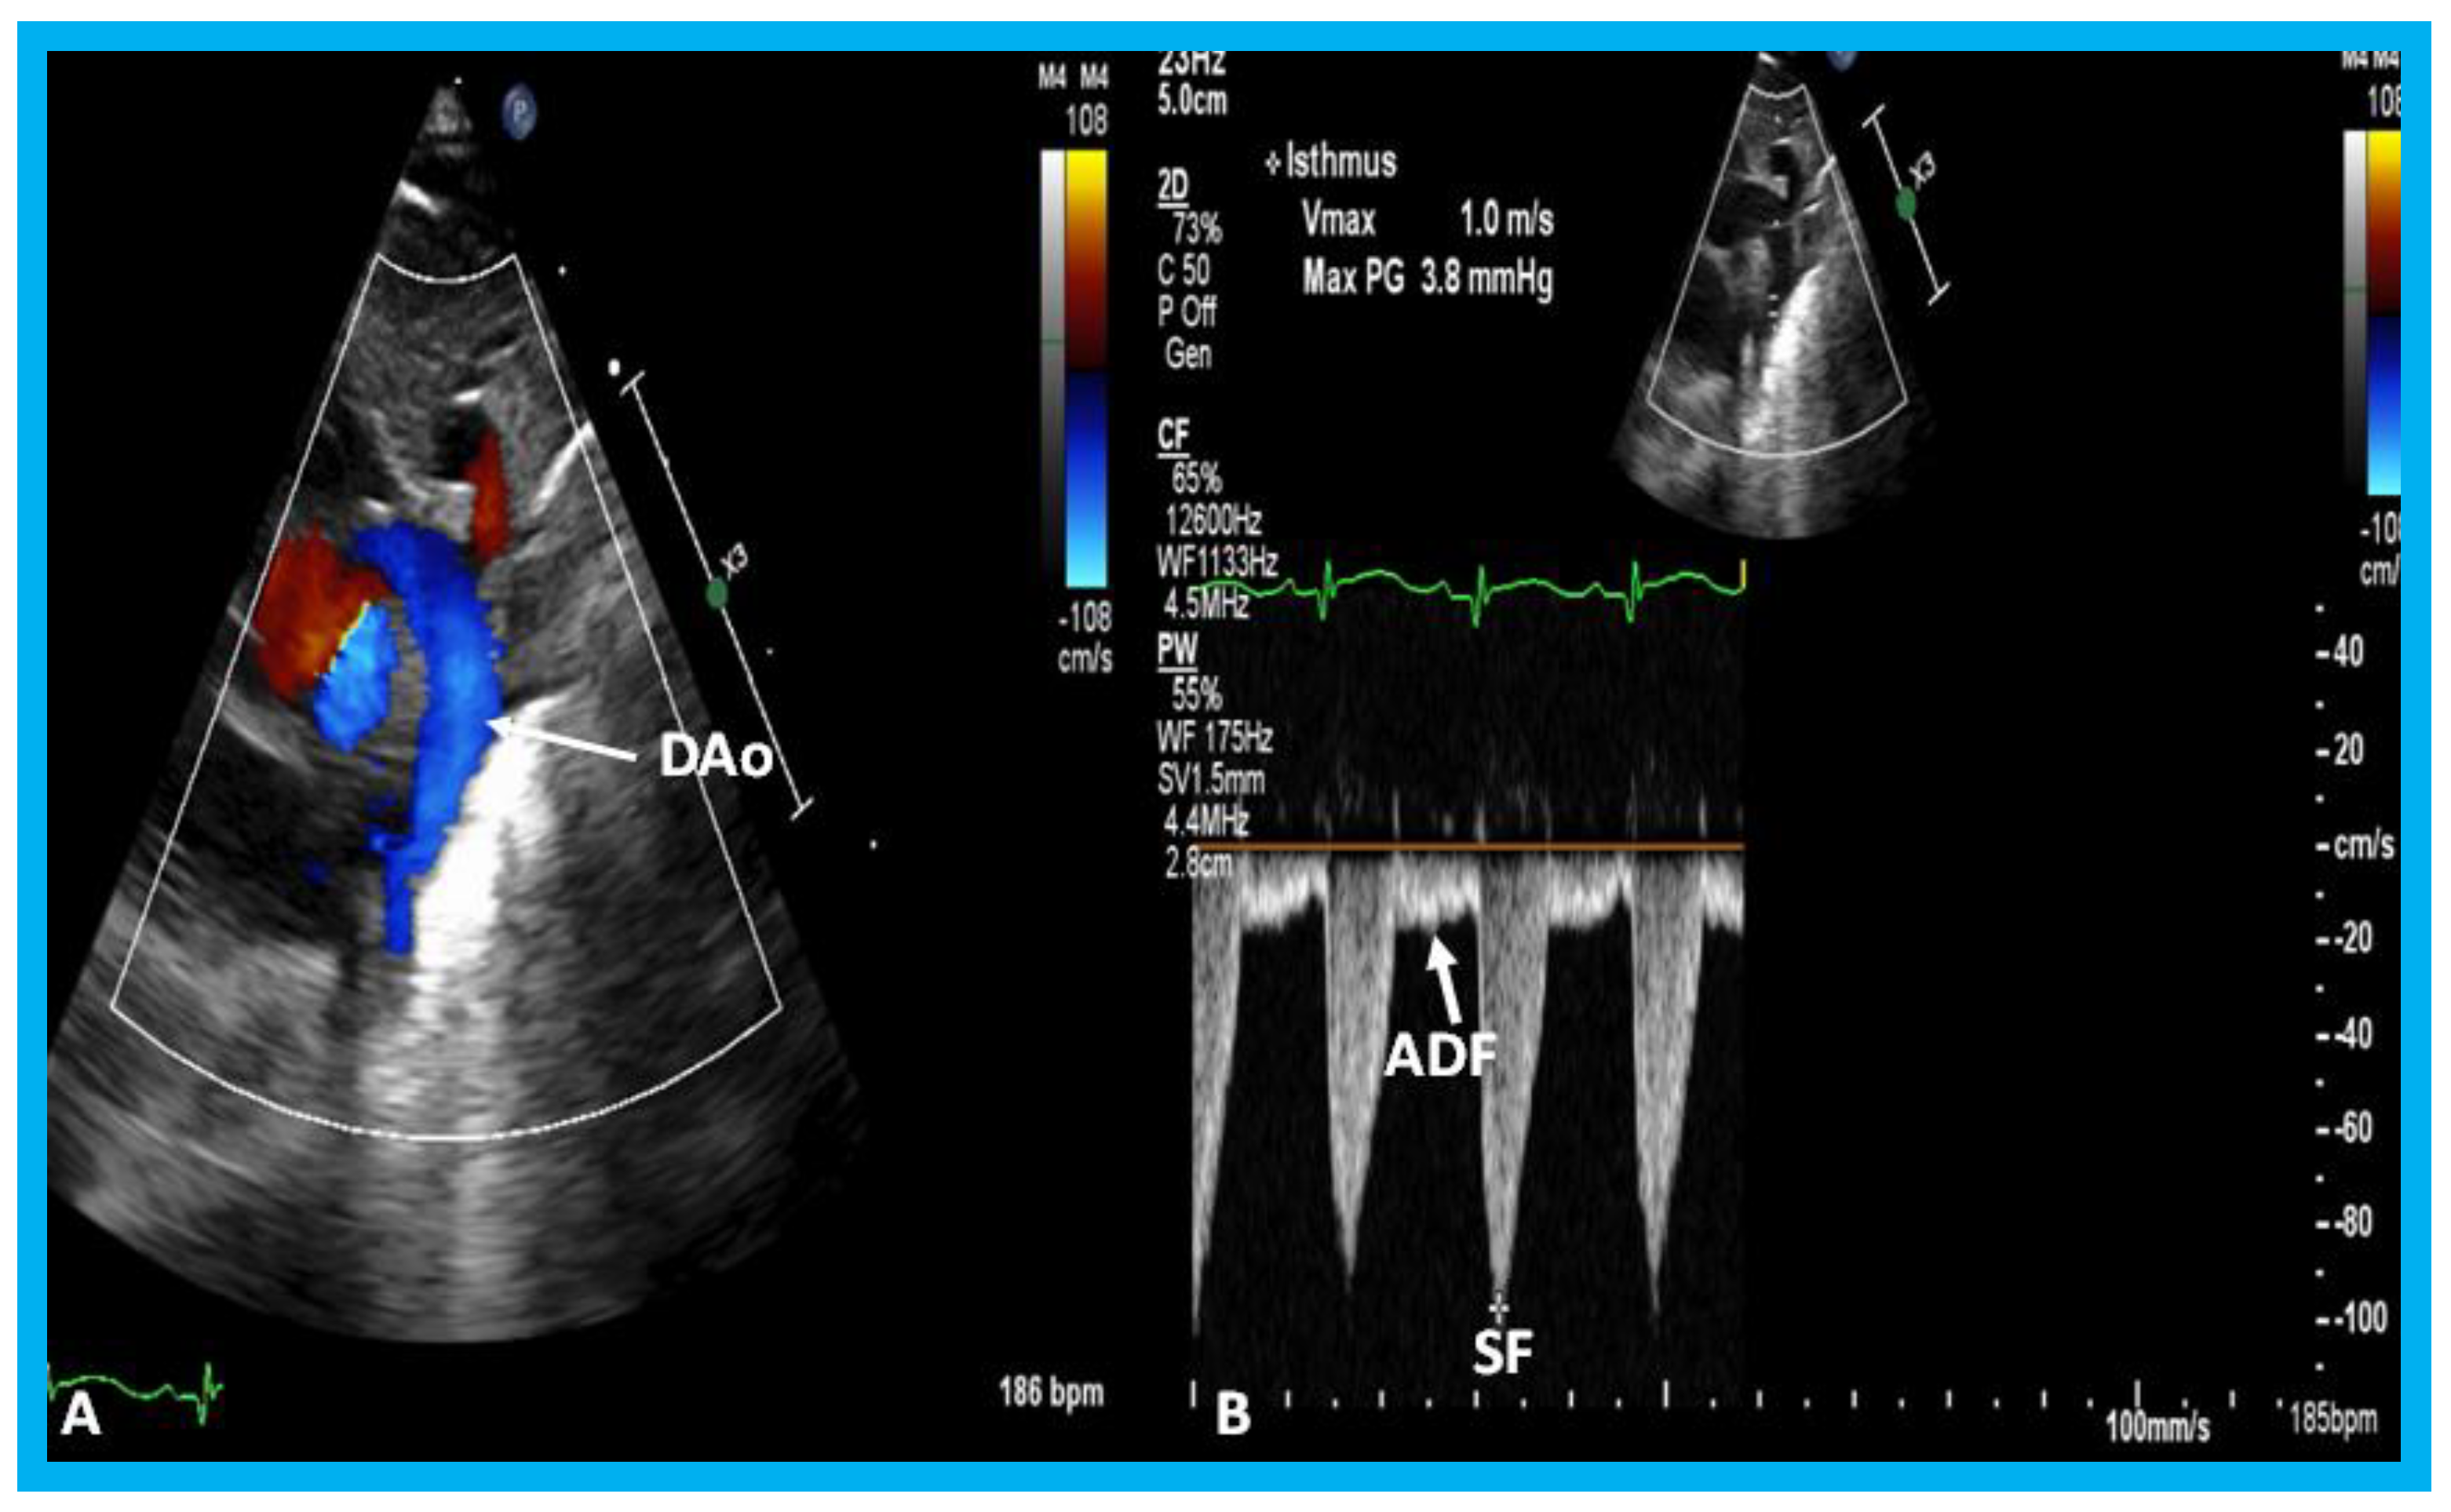

In small PDAs, the Minimal ductal diameter (MDD) is small and there is a high Doppler velocity across the PDA (Figure 32), while in large PDAs, the MDD is large and there is a low Doppler velocity across them (Figure 33). In moderately sized PDAs, these parameters are somewhere in between. The pulmonary artery (PA) pressures are usually normal in small PDAs, whereas the PA pressures are probably elevated in large PDAs. While the above statements are mostly accurate, the pressures in the PA also depend upon the magnitude of pulmonary parenchyma disease. Furthermore, in very low birth weight infants, the pressures in the PA may not be increased corresponding to the pulmonary parenchyma disease because of underdeveloped pulmonary vasculature in the premature.

Lastly, in small PDAs, normal diastolic anterograde flow is seen descending aorta (Figure 34), while in large PDAs, either no normal anterograde diastolic flow or retrograde diastolic flow (Figure 35) is seen in the descending aorta. Most of the medium-sized PDAs have normal diastolic anterograde flow in the descending aorta.